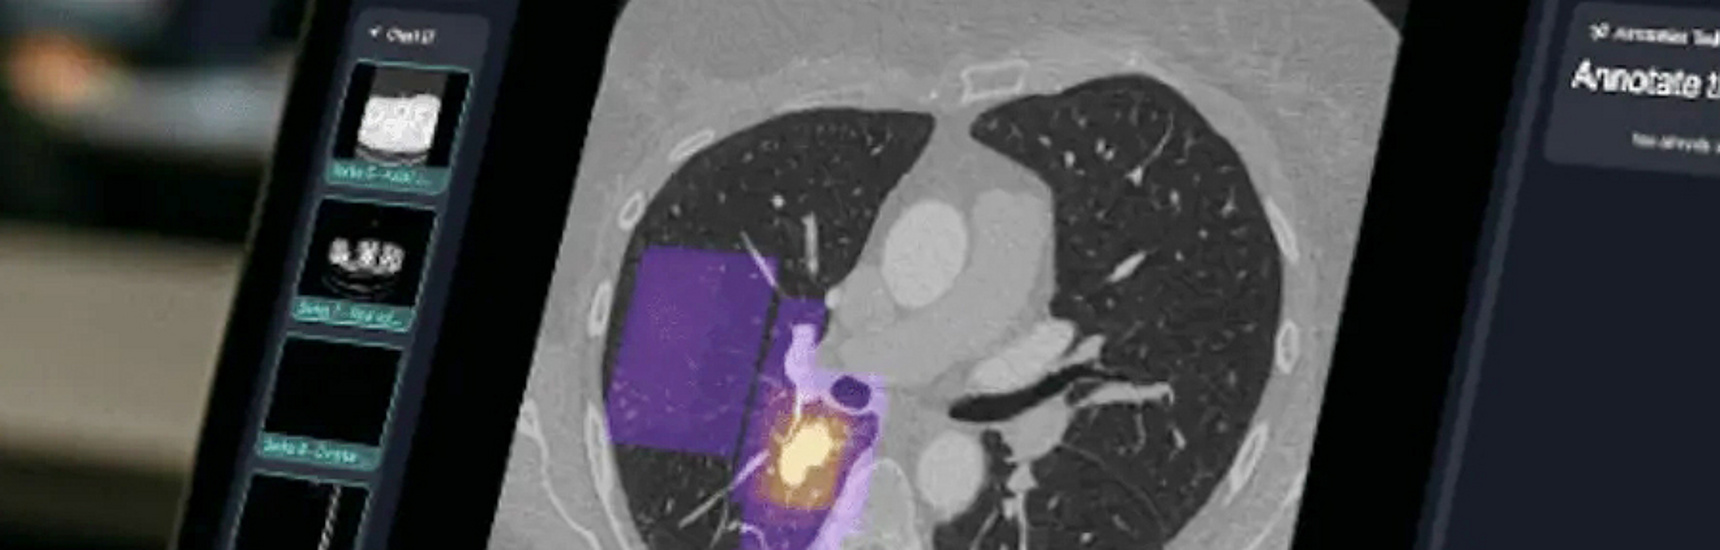

This is precisely where the award-winning project “Redefining Diagnosis: Interactive Radiology Teaching for the Future” comes in. “We want to take the crucial step from passive observation to active, diagnostic analysis,” says Sebastian Tschauner, Head of the Division of Paediatric Radiology at the Medical University of Graz. The centrepiece of the project is the implementation of the newly developed, web-based platform rapmed.net into the teaching of the “Imaging and Biostatistics” module. The application has recently made it possible to take the next evolutionary step: complex cross-sectional imaging techniques such as CT and MRI are distributed in real time by the lecturer to the devices of all students in the room. Students can log in via a QR code and work on the case presented on their own smartphone, tablet or laptop – as if they were sitting at a real small workstation. They can scroll through the layers of the respective examination, mark pathological changes directly in the image and submit their suspected diagnosis via interactive quiz formats.

Real-time feedback and ‘gamification’ elements, such as a consensus map showing the areas of an examination where the majority of students suspect a pathology, make the learning process dynamic and motivating. Both lecturers and students can explore the characteristic findings and features of a disease in greater detail. This not only promotes the recognition of clinical pictures but also trains diagnostic competence in a practical and sustainable manner. The project is more than just the implementation of new software. It is a comprehensive didactic concept that also puts several objectives of the university’s strategy into practice.